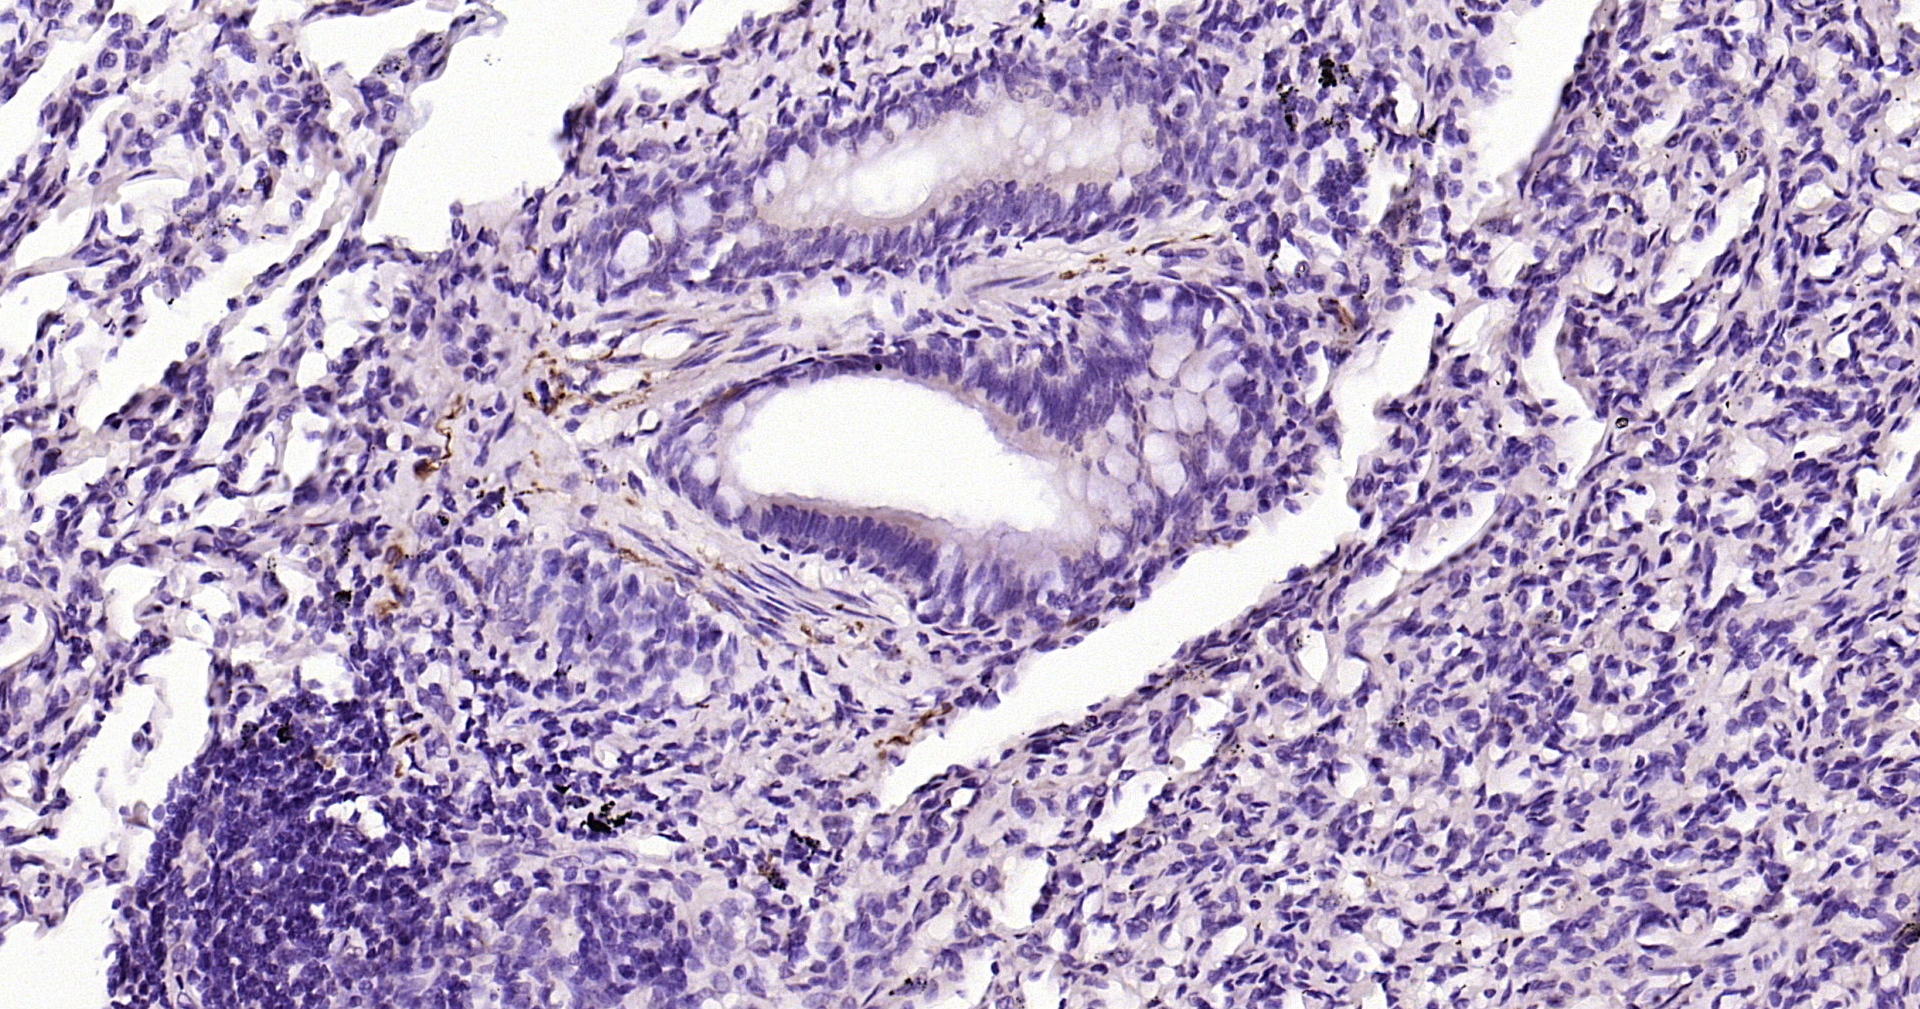

Applications IHC-P, IHC-F, IF(IHC-P)

IHC-P 1:200-1000

IHC-F IHC-F1:200-1000